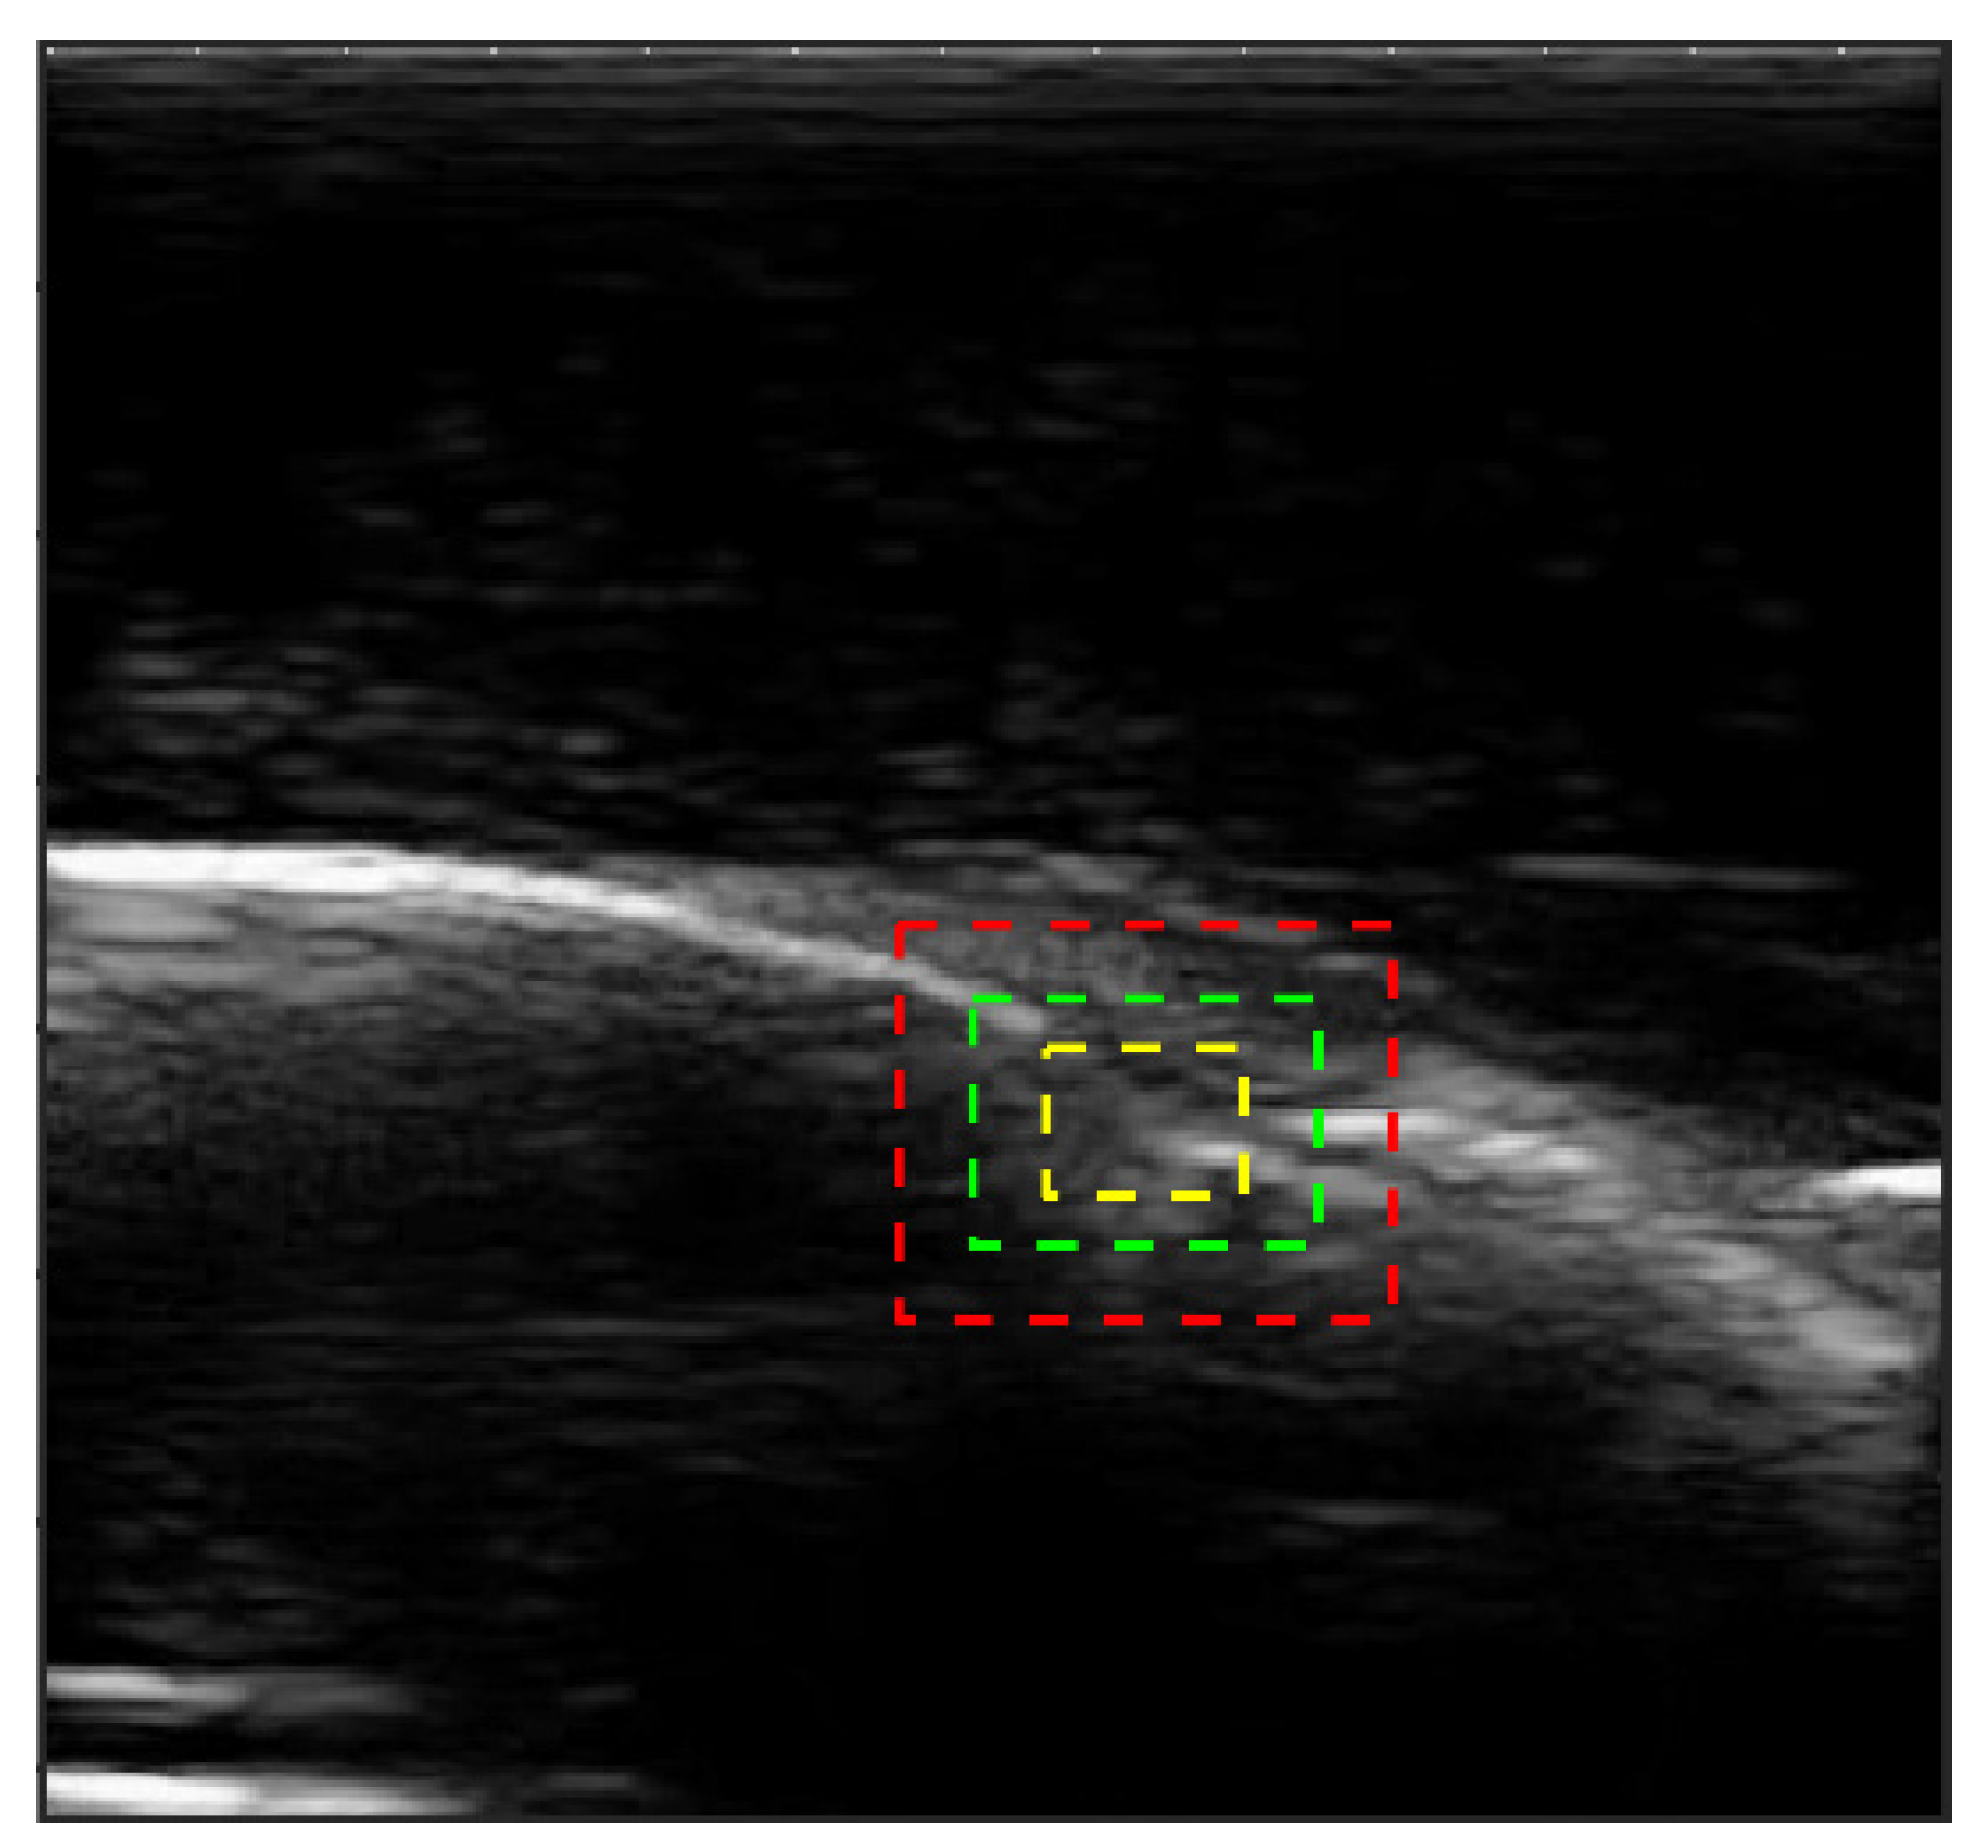

2.3. Image Segmentation

2.4. CEJ Selection